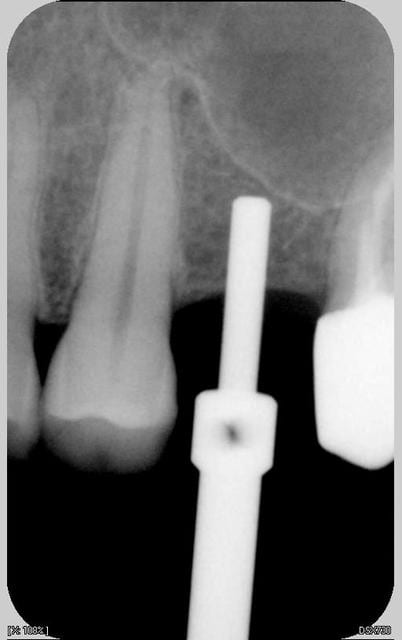

Les images de son cas sont superbes, mais la technique décrite par Growler n'est-elle pas dangereuse?

- pourquoi forage à... 8mm?????: selon Palti et... ,il faut arrêter son forage à 2mm environ de la corticale du plancher (d'où l'interet de connaitre avec exactitude la hauteur d'os sous -sinus: scan), pour être sur de ne pas perforer la corticale, la membrane....peut-on se fier à son seul sens "tactile"...?.

-pourquoi utiliser un autre foret que le 2mm, quand on trouve sous les sinus, dans 90% des cas, de l'os type I (selon mon humble expérience)et que l'on sait que toute la stab. primaire de l'implant repose sur son "accroche "dans les "quelques mm" d'un tel os et d'1 ou 2 corticales type "papier à cigarette" ,...??? pouquoi ne pas "élargir " le "tunnel créé au foret 2mm" avec des "expanseurs"(par exemple: dans la boite "à Summers" de hu-friedy, il ya des spreaders permettant depasser de 2 à 2,7, puis 2,7à 3,2, puis 3,2 à3,7, 3,7 à4,2...) : çà permet même de respecter un sous-forage de 7-8/10°mm pour un Tekka de 4 ou 4,5 ou 5...

- le fait de "pousser" le matériau "directement de 8 à 13mm, soit sur 5mm, ne présente-il pas non plus un risque pour la membrane...?